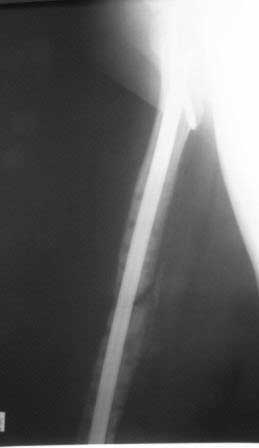

Результат нашего лечения: Произведено удаление пластины МIPO. Интрамедуллярный остеосинтез с рассверливанием канала. На 2-е сутки после операции больная передвигается при помощи костылей, с полной нагрузкой на оперированную конечность, болей в области перелома нет.

Фотографии в приложении.